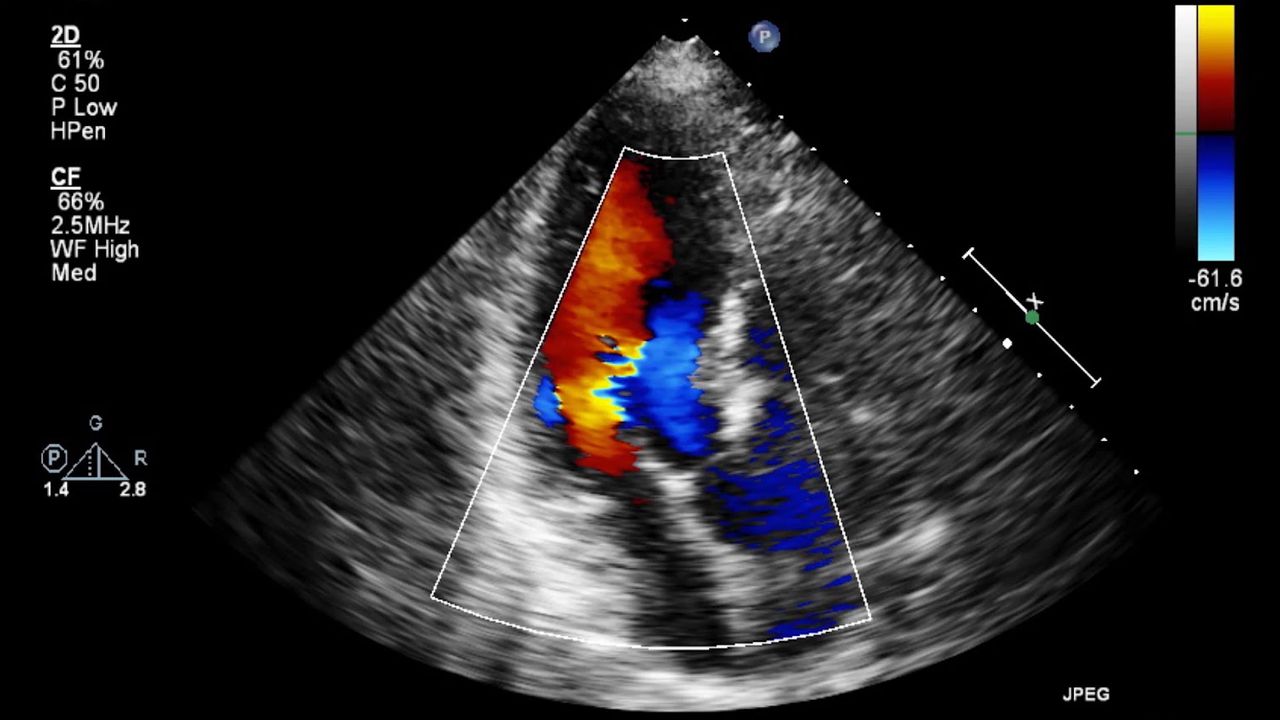

This test, which we call an "echo," makes images of your heart. It shows more detail than we see with an x-ray. It lets your doctor see how your heart beats. It can reveal problems within your heart.

The most common type of echo test is called a "transthoracic echocardiogram." We say "TTE." For this test, electrode stickers are put on your chest so your heart can be monitored. Then, an instrument called a "transducer" is moved around your chest. It sends high-frequency sound waves into your chest. When they bounce back, they are used to make an image.